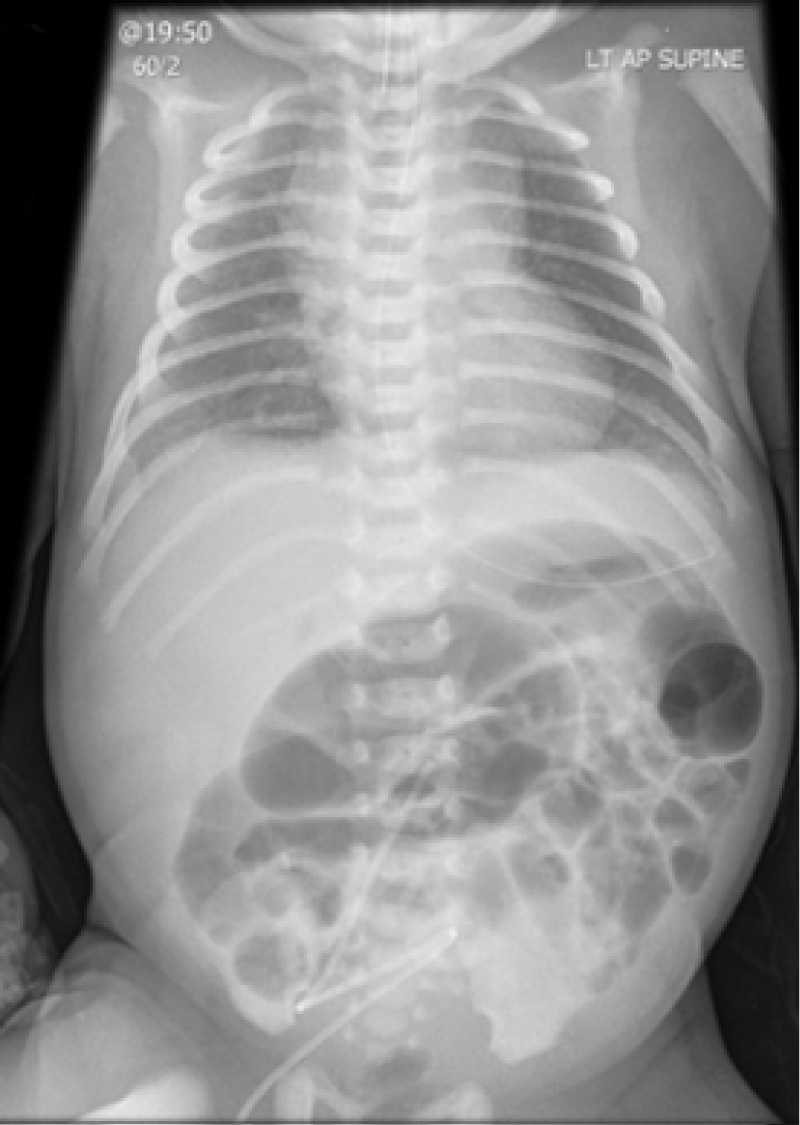

A term neonate was transferred from a Local Neonatal Unit to our surgical Neonatal Intensive Care Unit on Day 2 due to abdominal distension with radiological appearances suggestive of intestinal obstruction. He was born by Caesarean section with no risk factors for sepsis. He was intubated at birth for increased work of breathing and failed planned extubation on Day 1. Ventilation requirements were minimal and chest x-ray showed mild diffuse alveolar syndrome (Figure 1). Lung ultrasound on admission identified bilateral focal posterior lung consolidation, predominantly on the left side, surrounded with white lungs and with significant pleural effusion (Figure 2, Supplemental Video), highly suggestive of congenital pneumonia. C-reactive protein (CRP) reached a maximum of 15 mg/l. After 72 hours of antibiotics, he was successfully extubated with no respiratory support. Abdominal symptoms spontaneously resolved. An upper gastro-intestinal contrast study and a rectal biopsy were normal. Lung ultrasound performed after 7 days of antibiotics showed total resolution of the pleural effusion and consolidation.

Figure 1: Chest and abdominal x-ray showing mild RDS and dilated intestinal loops